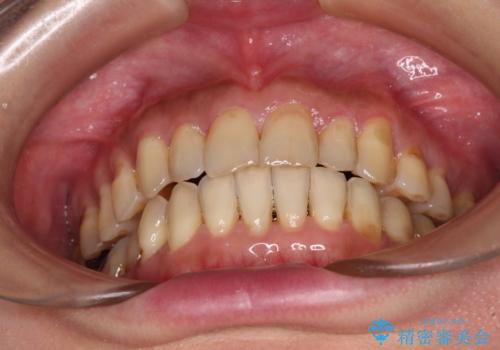

- 歯列不正と、どこで咬んで良いのか分からない咬み合わせを気にして来院された患者様です。

下顎骨は左側にシフトしており、咬み合ったときには奥歯と前歯の一部しか接触していない状態でした。

骨格的な左右差は歯列矯正は改善できないため、上下歯列が全体的に接触することをゴールとしてインビザラインにて矯正治療を行うこととしました。